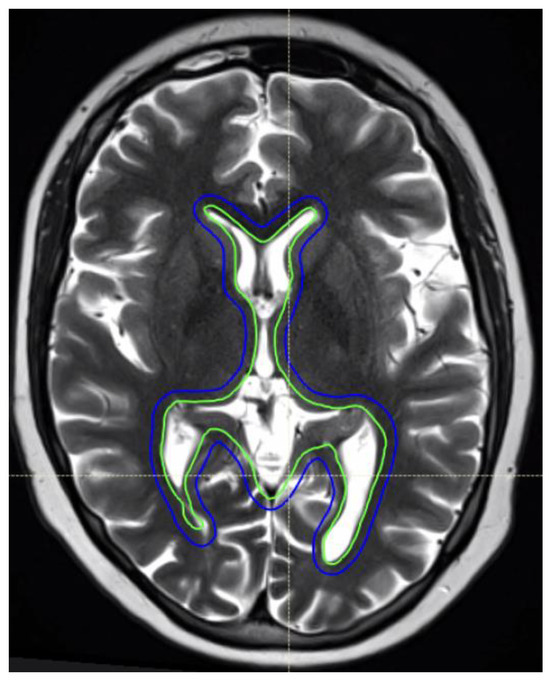

4.2. Hippocampal-Sparing Technique

- Gondi, V.; Tolakanahalli, R.; Mehta, M.P.; Tewatia, D.; Rowley, H.; Kuo, J.S.; Khuntia, D.; Tomé, W.A. Hippocampal-Sparing Whole-Brain Radiotherapy: A “How-To” Technique Using Helical Tomotherapy and Linear Accelerator–Based Intensity-Modulated Radiotherapy. Int. J. Radiat. Oncol. 2010, 78, 1244–1252. [Google Scholar] [CrossRef]

- Sethi, R.; MacDonald, S. Hippocampus avoidance in pediatric patients. Neuro-Oncology 2019, 21, 1093–1094. [Google Scholar] [CrossRef] [PubMed]